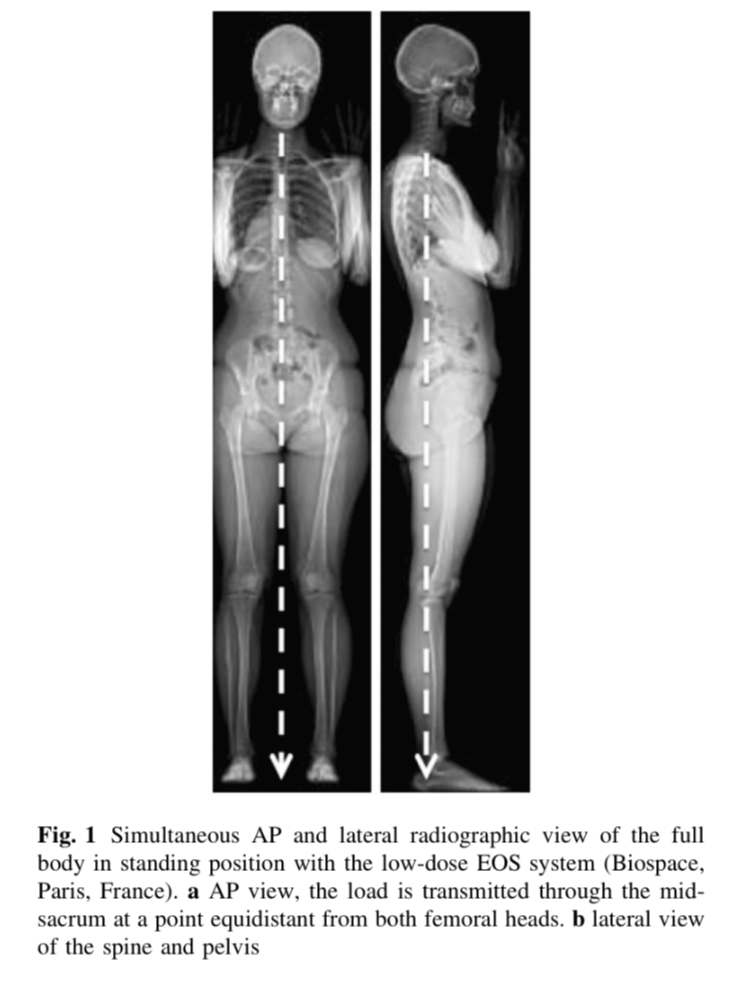

인간에 만드는 직립 자세는 특징적인 척추 곡선과 함께 골반의 확장 및 수직화를 가져왔고 척추를 지지하기 위헤 근육의 구조를 자신의 체형에 맞게 변형 시겼습니다. 인간의 이족보행은 독점적이고 안정적이며 인체공학적인 자세입니다. 사람의 직립 자세의 전환은 골반이 움직임의 핵심 구조가 되는 결과를 가져왔습니다. 골반 척추는 몸통과 뒷다리 사이의 연결을 형성합니다. 대퇴골두는 움직임이 많기 때문에 골반 척추의 공간적 방향에 중요한 역할을 합니다. 대퇴골두는 골반에 가해지는 흉요추 하중이 하지로 전달되는 지점을 구성합니다. 척추를 지지하고 형성하는 천골은 몸통에서 골반으로 하중이 전달되는 지점입니다. 전방 척추와 골반의 위치는 직선적입니다. 정상적인 척추는 천골과 치골 결합의 중앙을 통과하는 중앙 축 갖습니다(그림 1). 정상 골반은 수평이며 대칭 지점이 같은 높이에 있습니다. 그러나 시상면 골반 위치의 기하학은 더 복잡합니다. 골반의 시상면 균형을 특성화하려면 제약 조건의 전달과 관련된 생체역학적 특징을 기반으로 특정 매개변수를 정의해야 합니다.